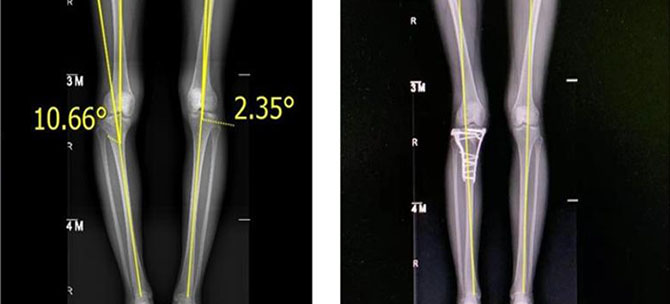

胫骨高位截骨手术,适用于因外伤或原发疾病导致膝关节单纯内侧磨损及下肢力线显著异常的患者。手术在完全不移除病人原有的膝关节软骨及骨骼基础上,以纠正膝关节生物力学轴线,来减轻内侧骨髁的受力。具有:校正下肢畸形、术后功能快速恢复、延后膝关节置换时机、改善下肢压力分布等临床优势。